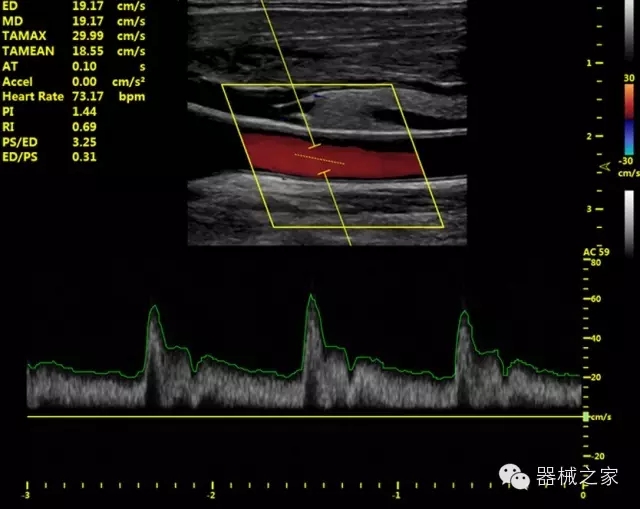

臨床圖片賞析

·智能感知組織特異性的VTissue技術(shù),結(jié)合特有高達(dá)22MHzXcen線陣探頭, 以及獨(dú)有敏感的RF射頻血流提供了優(yōu)異臨床圖像;

·獨(dú)有RF敏感血流使得心臟血流完美呈現(xiàn);